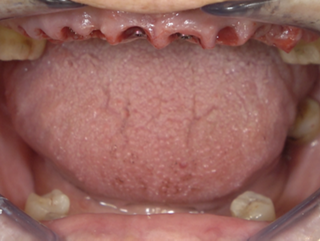

Guided FP1 maxillary rehabilitation with Straumann® STARconcept™ and Straumann iGuide™. A clinical case report by Dr. David Norré, Belgium.

Facially driven Smilecloud design with a focus on preserving tissue and bone. Planned in Smile in a Box and executed with the iGuide protocol; shared pin positions align the drill and prosthetic guides for chairside pickup of the pre-designed provisional. Day-5 follow-up shows the screw-retained provisional in place.

• Strategic extractions for guide seating on anchor teeth.

• Passive-fit check of the surgical guide before drilling.